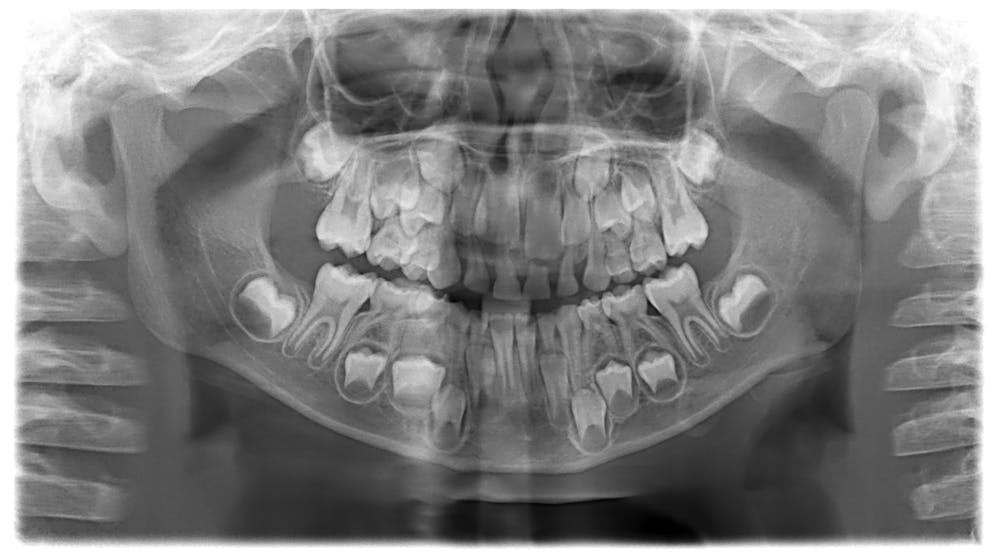

Rommel , eds ) , Vol. This child's skull shows rows of adult teeth waiting to replace baby teeth. A newly developed tusk has a smooth enamel cap that eventually wears off.

There are two sets of teeth in this skull and it is because the ‘milk’ or ‘baby’ teeth will shed so the new will come. 15 – 72. Erupted above the gums or almost so, These first teeth are known as milk (or deciduous) teeth.

The picture is described as "A child’s skull before losing baby teeth". Milk Teeth - Premolars & Molars. Sideshows have fascinated audiences for centuries, first enthralling them during the end of the 1800s and beginning of the 1900s.

In Skeptics.SE, a question regarding the skulls of children arose. This process continues until the 6th and sometimes 7th molar appears. Depicting a scary skull where the permenent teeth are "hidden" inside the jaws and the milk teeth are in the their place.

The young animal, whether male or female, has 24 temporary teeth, commonly called milk teeth, as they are much whiter than the permanent teeth. A child's skull, before their milk teeth fall out. After the first two teeth are gone, parts of the two adjacent teeth are being worn down in each half of the jaw.

As a group, reptilian skulls differ from those of early amphibians. The deciduous dentition is also known as the milk teeth. Tooth buds form in a baby’s gum in the womb, so they are still hidden away like in this picture.

There's a picture on Pinterest depicting a child's skull with all deciduous teeth (baby teeth) still attached, and adult teeth showing in a quite developed stage underneath:. After all milk teeth fall out, and the permanent teeth "rise", do the holes left by them filled up, or do we go around with holes in our jaws?. Saved by Jamie Lutz.